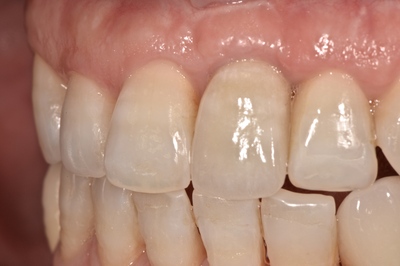

前歯部へのインプラント治療。

外傷=転倒による歯牙破折により抜歯。

術後、まだまだ3年程度だが。

指摘されなければどの部分にインプラント治療行われているか分からない。

前歯部へのインプラント治療の難易度は非常に高い。

マイクロスコープ下による歯周外科(主に結合組織移植)を用い、外傷による軟組織欠損の回復を行っている。

外傷による歯肉裂傷の跡が残存。